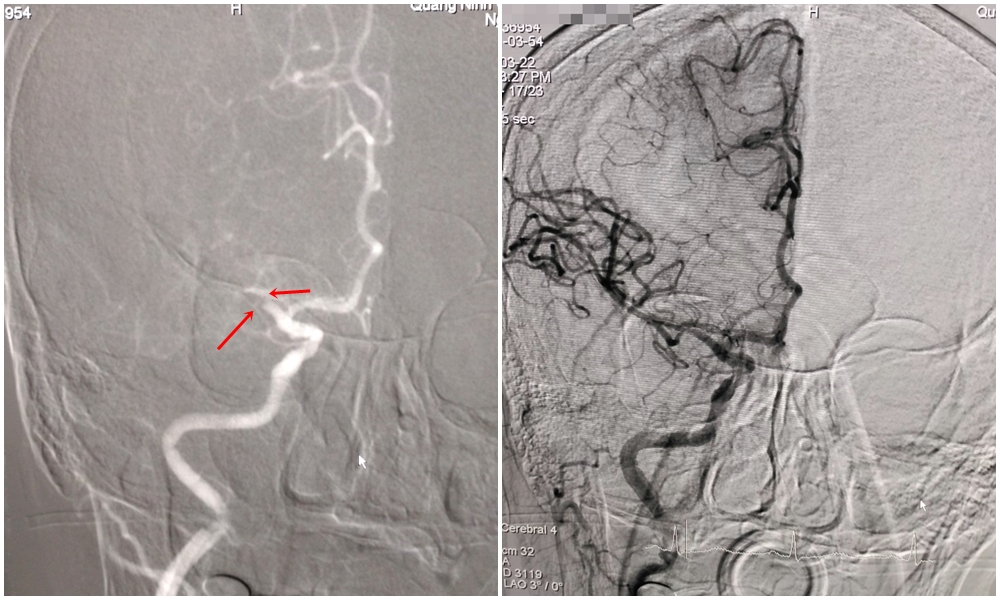

Hình ảnh tắc động mạch não giữa phải tái thông trở lại ngay sau khi được can thiệp lấy huyết khối.

Bệnh viện tiếp nhận bệnh nhân trong tình trạng lơ mơ, thất ngôn, liệt hoàn toàn nửa người trái, cơ lực tay chân trái 0/5, tiên lượng nặng, đe dọa sự sống. Qua kết quả phần mềm RAPID, các bác sĩ quyết định lấy huyết khối động mạch não bằng dụng cụ cơ học. Kíp can thiệp khoa Chẩn đoán hình ảnh trong trang phục bảo hộ đã tiến hành lấy huyết khối tái thông mạch não bị nghẽn dưới sự hỗ trợ của hệ thống máy chụp mạch xóa nền 2 bình diện DSA. Ca can thiệp cấp cứu diễn ra thuận lợi thành công sau gần 1 tiếng thực hiện.